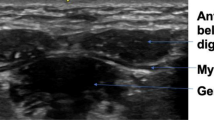

The aim of this study was to compare CSA values obtained by MRI and ultrasound for all submental muscles. However, the geniohyoid and mylohyoid muscle boundaries could not be visualized sufficiently to allow measurement of the CSA from MRI images (Fig. 1); hence, no comparison could be made for these muscles, although these measurements could be obtained from ultrasound images (Fig. 2). CSA measurements of the mylohyoid muscle were not possible using ultrasound images (Fig. 2), as the lateral borders of the muscle were not visible. Therefore, only calculation of one-dimensional (1D) thickness of the mylohyoid was possible from ultrasound images (Fig. 2). As the clarity of the mylohyoid muscle was not sufficient to measure 1D thickness using MRI images (Fig. 1), analysis was limited to comparison of the anterior belly of the digastric muscle.

CSA measurements of the geniohyoid muscle and thickness measurements of the mylohyoid muscle were not possible on MRI images due to poor border delineation (Figs. 1 and 2). These muscles could be differentiated and measured from ultrasonographic images, suggesting that there is a difference in the sensitivity of the two methods for demarcating these muscles. The acquisition of MRI images in this study required a longer duration of movement inhibition (3 min) than ultrasound image acquisition (0.3 s). As the submental muscles are activated during swallowing at least once every minute [28], it is likely that image clarity was compromised to a greater degree for MRI than for ultrasound. CSA measurements were taken from the muscle’s belly in both ultrasound and MRI images. As most movement occurs at the muscle’s belly, controlling movement is essential for CSA measurements from this location, which suggests that the advantage of rapid acquisition time of ultrasound is especially applicable in this case. The difference in signal generation between the two methods also may contribute to the superior image quality documented for ultrasound in this study. Because ultrasound uses the change in reflective properties of adjacent tissues, it may be more sensitive to the muscle borders in this confined space than MRI, which generates a signal based on proton density. In addition, because of scanning schedules, image acquisition duration, and limited funding for the acquisition of the MRI images, it was possible to scrutinize and repeat image acquisition if movement artifact was detected during only the ultrasound procedure.